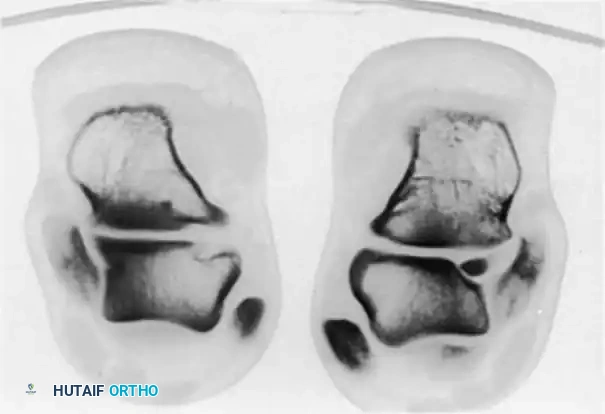

Fig. 2: Talar neoplasms mimicking chronic ankle sprain. Eosinophilic granuloma of the talar body.

Talar Neoplasms

Benign and locally aggressive neoplasms have a documented predilection for the talus and can produce insidious, deep-seated pain that mimics chronic sprains.

* Eosinophilic Granuloma & Simple Bone Cysts: Can cause structural weakening and microfractures.